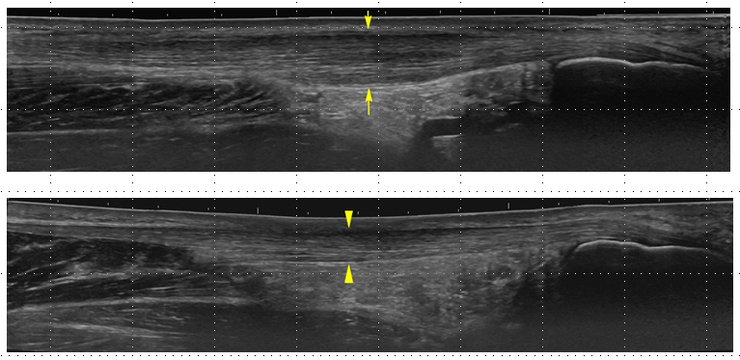

▲ 그림 3. 건증(tendinosis)에서의 아킬레스건과 정상 아킬레스건

<그림 3>의 위쪽 영상은 Achilles 건증으로 인해 아킬레스건이 두꺼워진 상태를 보여줍니다. 아래쪽 사진은 동일 환자의 건측 아킬레스건입니다. 위쪽 사진의 건(tendon)은 9㎜ 정도의 두께를 보입니다.